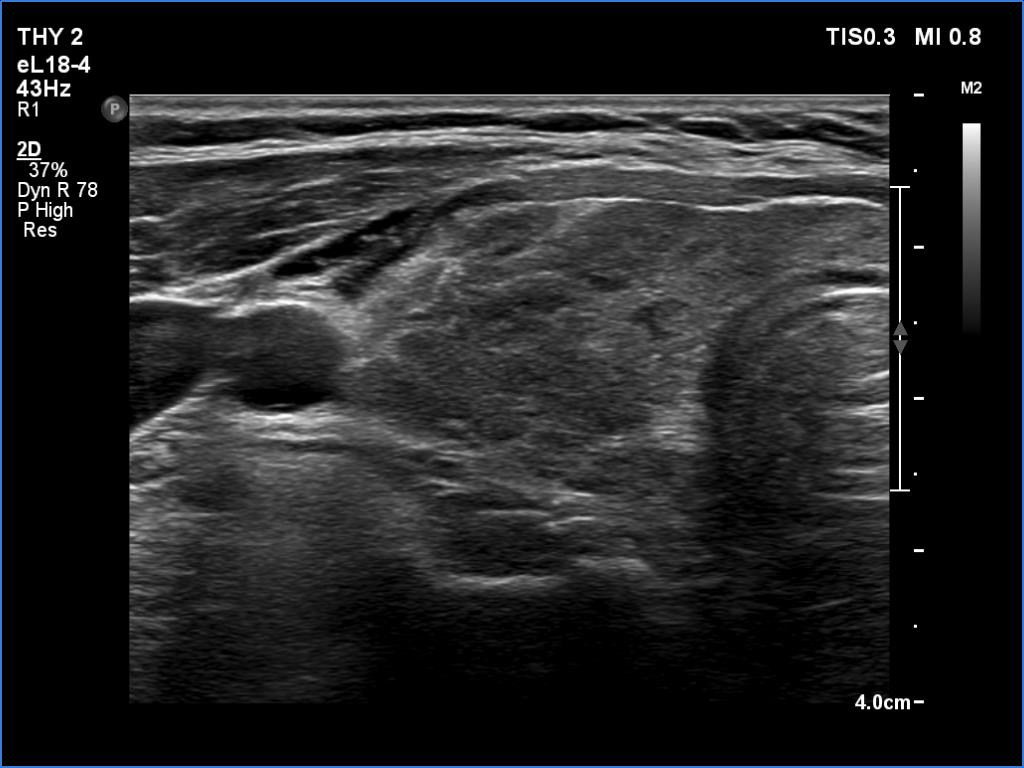

A patient operated on Graves' disease then received radioiodine therapy - case 321

After the surgery before the radioiodine treatment

After the radioiodine treatment

The patient had a recurrent hyperthyroidism 15 years after a bilateral subtotal resection performed because of relapsing Graves disease. Several months after the first visit, the patient underwent on radioiodine treatment. The right images were recorded 5 years after the isotope therapy.

In surgically treated thyroids, the histopathological findings must be taken ito account in order to avoid mispretating discrete lesions. If the previous histopathology did not find nodule than an ambiguous lesion is very rarely a true nodule.

The echonormal areas which surround the hypoechoic lesion can be tracked up, down and sideways, therefore these do not correspond to thyroid tissue but to connective tissue.